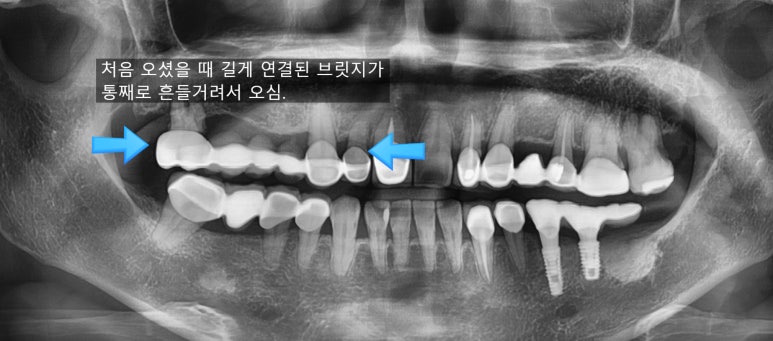

어금니부터 일부 앞니까지 연결된 긴 브릿지가 흔들려서 임플란트를 하게 된 케이스

처음 오셨을 때 상태

앞니 뿌리쪽까지 많이 썩어서 삭아 들어가서

앞니 브릿지가 붙을 곳이 없어서 흔들거리고 빠져서 온 상태입니다.

어금니쪽도 다른데서 한 임플란트가 찢어져서 임플란트 머리를 못 올린 상태였고

어금니도 몇 개 상실한 상태입니다.

치료전( 앞니 브릿지 떨어져서 덜렁이는 상태, 다른 곳에서 임플란트 찢어져 실패해서 잇몸에 묻혀진 상태)